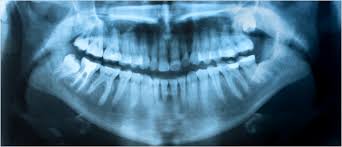

V tokratni Secundi Conversatio gostimo dr. dent. med. Damirja Škripca, ki je v Sloveniji oral ledino na področju laserskega zobozdravstva. Naš cenjeni gost med drugim že vrsto let opozarja na problem amalgamskih plomb in toksičnosti fluora. O tem, kaj je biološko zobozdravstvo in zakaj je potrebno za neboleče puljenje zob obvladati met kladiva, pa več v oddaji.